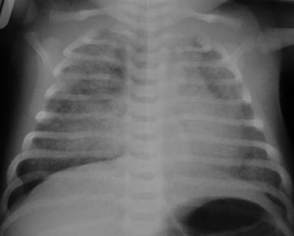

Taquipneia transitória do neonato (síndrome do desconforto respiratório tipo 2): estrias peri-hilares e fluido na fissura horizontal à direita

Do acervo de Ponthenkandath Sasidharan, MD; usado com permissão